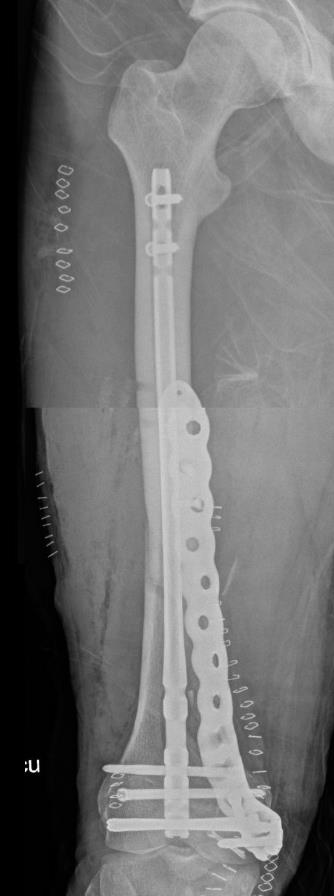

Summary Designed with SOMA (Stryker Orthopedics Modeling and Analytics) which includes a database with CT scans from hospitals across the world and state of the art algorithms that analyze shape variability, bone density, and implant fit Designed to link with the T2 Alpha Femur Retrograde Nail when using nail plate combination fixation Eight distal T20 screw holes, including 1 linking hole and 1 AP hole designed to capture Hoffa fragments Related Implants The Pangea® Femur Reconstruction System includes Lateral NPC Plate Medial NPC Plate (this topic) T2 Alpha™ Femur Retrograde Nailing System Design Tapered end allows for atraumatic submuscular insertion Staggered screw holes designed to enable surgeon to choose points of fixation and allows for placement of screws around an intramedullary implant or a prothesis AP hole screw hole trajectory that is designed to capture a "Hoffa Fragment" (Posterior Medial Condyle) Variable-angle screw holes circular universal holes accept non-locking screws, and locking screws within a 30° cone Proximal twist metadiaphyseal twist allows for screw placement anterior to posterior Linking hole designed to allow for seamless linking of the plate to a T2 Alpha Femur Retrograde Nail using an AlphaLink Dowel Indications Indications partial articular medial tibial plateau fractures medial plateau fragments in bicondylar tibial plateau fractures metaphyseal fractures epiphyseal fractures extra-articular proximal tibial fractures Contraindications active or suspected infection at the surgical site severe local inflammation around the operative area hypersensitivity or allergy to implant materials inadequate soft-tissue coverage over the implant Anatomy Osteology medial tibial plateau medial femoral condyle intercondylar eminence attachment point for cruciate ligaments tibial tuberosity insertion of the patellar tendon Muscles anteromedial tibia sartorius gracilis semitendinosus popliteus stabilizes and unlocks the knee Ligaments medial collateral ligament anterior cruciate ligament posterior cruciate ligament medial meniscus Approach Surgeons may use a standard medial, medial parapatellar, or medial subvastus approach to the distal medial femur Technical specifications Plate material type II anodized titanium (Ti6Al4V) Two plate lengths 155mm and 265mm Plate thickness 5mm Left and right anatomic options Screws Multiaxial locking 5.0 (14-120 mm) 4.0 (14-95mm) 5.0 (10-20mm) Cortex 4.5 (14-150mm) Cancellous 6.0 (20-150mm) 6.0 (30-150mm) 6.0 (45-150mm) Cable plug washer AlphaLink Dowel 50-90mm